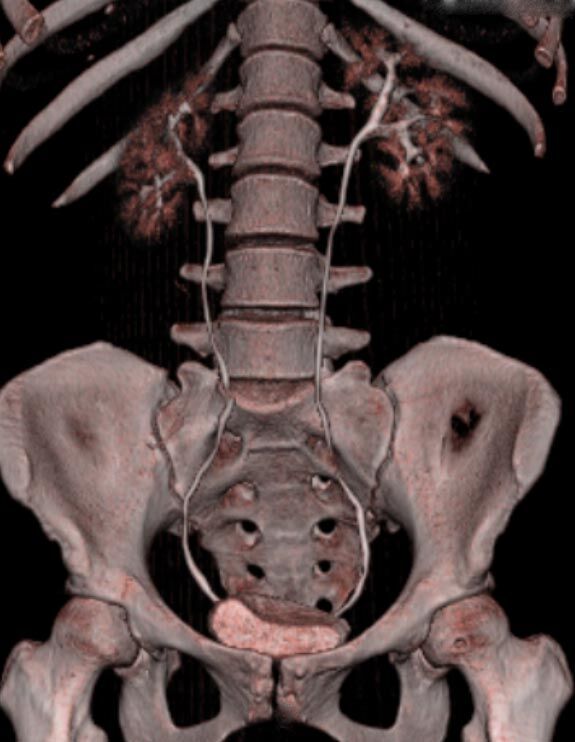

Abdomen (Bauch und Becken)

• Diagnostik von entzündlichen und tumorösen Erkrankungen der Bauchorgane

• Diagnostik von akuten Notfällen wie Darmverschluss, Hohlorganperforation oder Traumafolgen

• Darstellung der großen Gefäße zur Erkennung von Gefäßverschlüssen (z. B. Mesenterial - Arterienembolie oder Einengungen von Gefäßen (z. B. Nierenarterien)

• Darstellung und Therapieplanung von Aneurysmen (CT- Angiographie)

• Virtuelle Kolonographie zur Darstellung des Dickdarmes z. B. bei Kontraindikation zur Darm-Spiegelung oder nur unvollständig durchführbarer Koloskopie.

Spezielle Software ermöglicht jetzt zum Beispiel:

• verbesserte Bildqualität bei Patienten mit Implantaten (z. Bsp. Hüftendoprothesen)

• besonders hochauflösende, strahlendosissparende Darstellung aller Skelettstrukturen

• mehrdimensionale Darstellung vasculärer Strukturen mit zahlreichen Auswertungstools